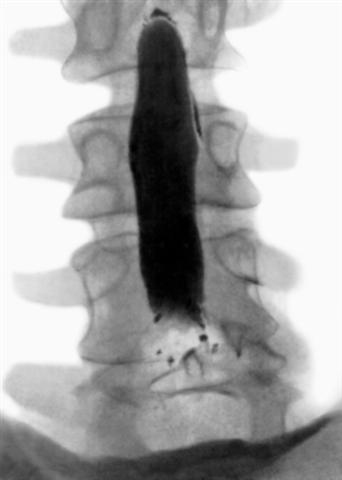

Рис. 4а). Миелограмма поясничного отдела позвоночника в норме: прямая проекция.